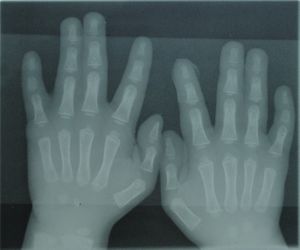

Radiograph of Type 1 Syndactyly